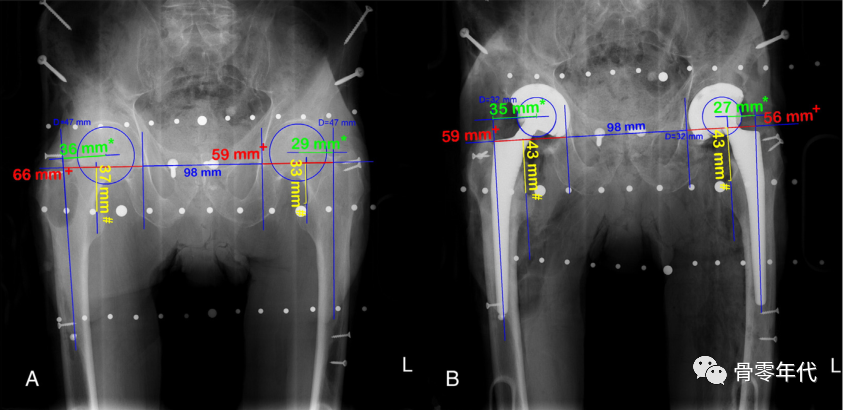

然后画一条水平线连接两个泪滴的最下面的边缘。对于肢体长度,在小转子上选择一个双侧等效的点,并垂直于水平连接(图A)。为了确定偏移量,然后在每个股骨颈上选择一个点,大约在预期的颈部切口水平。从颈部这一点开始画一条线,平行于泪滴间线到坐骨边缘(图B)。

(A)内收和内旋对右髋关节偏移量的影响。与左侧臀部相比,这会产生一种减少偏移量的感觉。(B)骨盆倾斜对肢体长度和偏移量的影响,通过减小髋关节抬高时的偏移量和肢体长度,而对向下旋转的髋关节产生相反的影响。

通过比较术前(A)和术后(B)骨盆的放大校正X线片,评估LL(#)、GO(+)和FO(*)的变化.